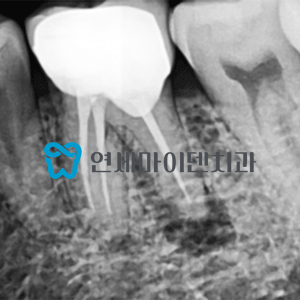

치료 사례